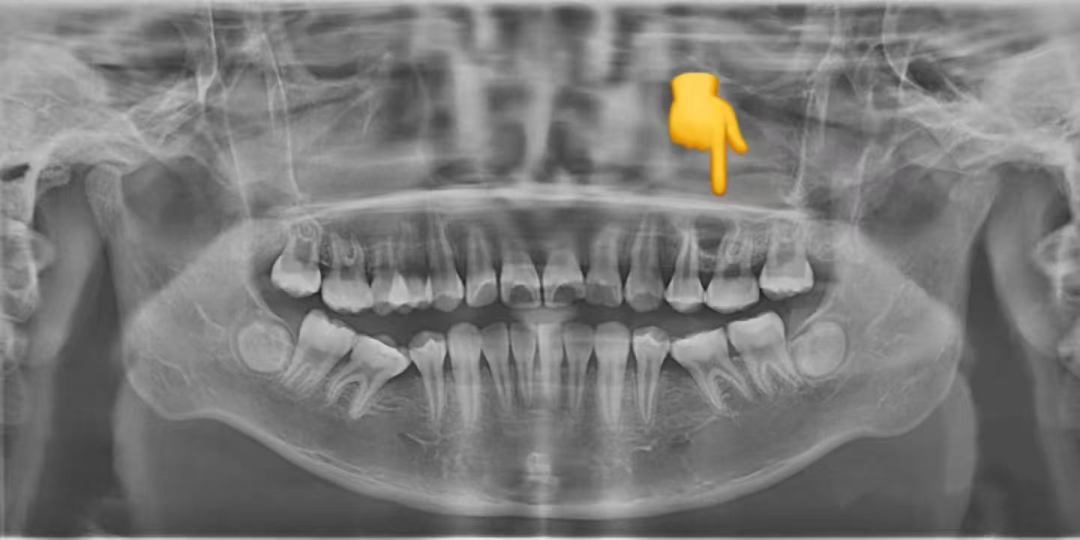

简单来说,埋伏牙就是牙齿在萌出的过程中,因为各种原因没能顺利长到口腔里,而是 “藏” 在了颌骨里面。这就好比一颗种子被种下去后,却始终没有破土而出,默默待在土壤里一样。

如果大家怀疑自己有埋伏牙,一定要及时去正规的口腔医院进行检查。通常情况下,拍个 X 光片就能清楚地看到牙齿的情况了。